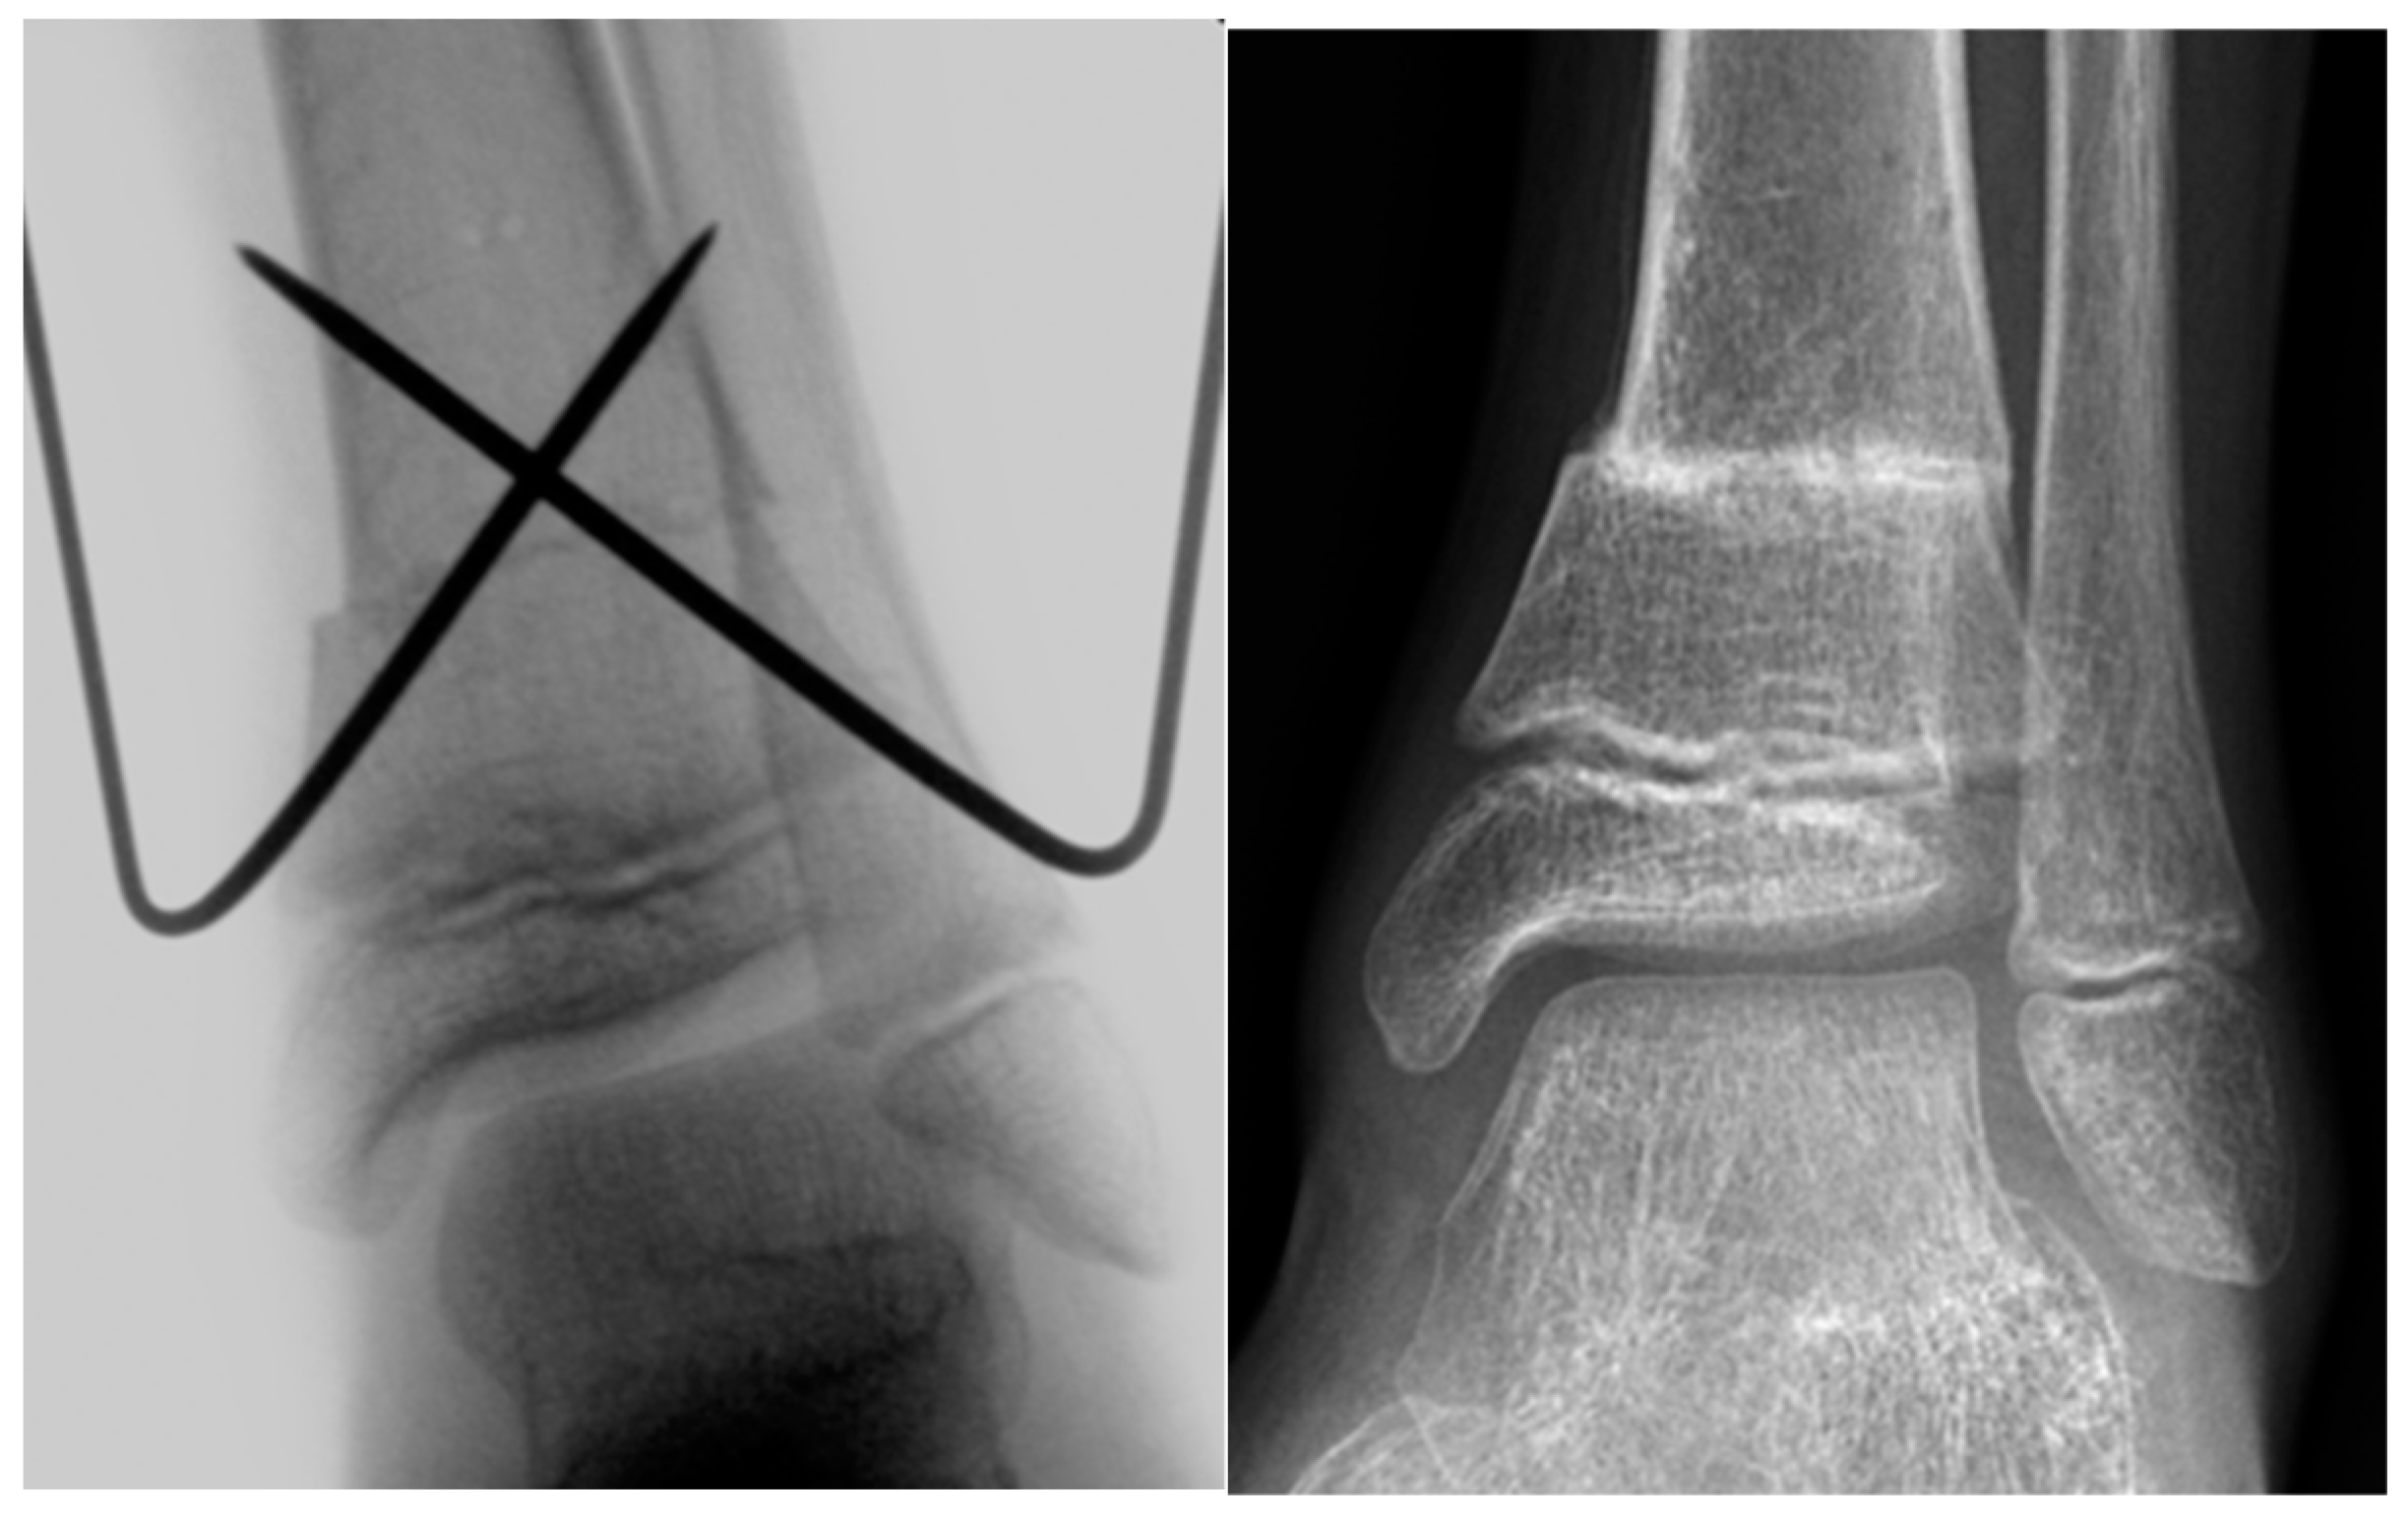

Figure 1.

Intraoperative X-ray image and X-ray image obtained at 2 months after SMO fixed with K‑wires in an 11-year-old male patient with increased external torsion of the tibia.